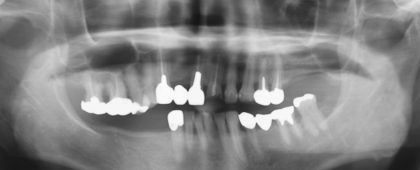

治療前 |

向かって右側上あごにインプラントの治療をおこなう予定ですが、骨の高さが不足しています。 |